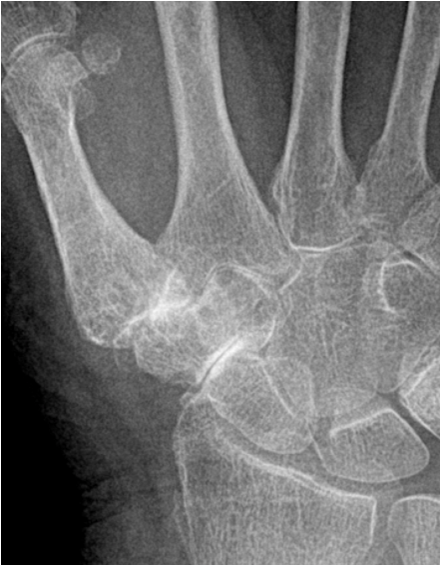

In the hand there is typically involvement of the trapezium-scaphoidal joint and the first carpal-metacarpal joint. In addition, there is involvement of the distal interphalangeal joints of the fingers with lesser changes at the proximal interphalangeal joints and the metacarpal-phalangeal joints.

Fig. 14. Typical degenerative changes in the hand: A) Joint space narrowing and subchondral sclerosis of the trapezoidum-scaphoidal joint and the first carpal-metacarpal joint. B.) Degenerative arthritis of the distal interphalangeal joint showing typical osteophyte formation, joint space narrowing and increased sclerosis.